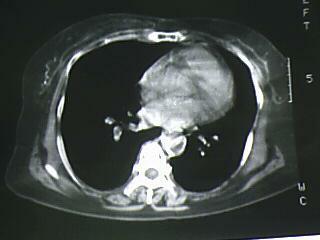

以下是引用杀毒软件在2009-4-14 17:52:00的发言:[br]考虑---右肺继发型肺结核---纵隔淋巴结多发钙化----左肺支扩

以下是引用黑白光影在2009-4-14 20:36:00的发言:[br]右肺继发型肺结核;左下慢性支气管炎性病变。